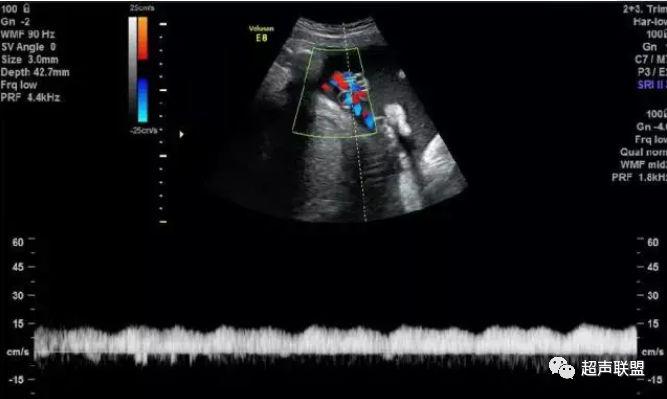

图9 脐静脉搏动

胎儿宫内缺氧严重时脐静脉出现搏动。

6、脐静脉:脐静脉搏动(见于严重的胎儿宫内缺氧);

4、脐静脉搏动。